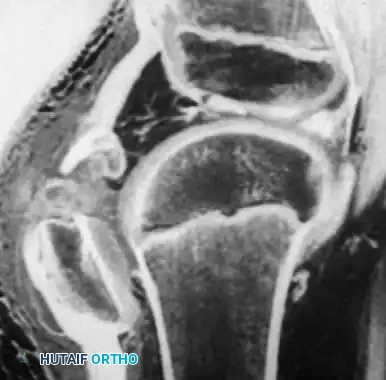

Surgical Warning: When a pediatric patient presents with an inability to perform a straight leg raise, a palpable infrapatellar defect, and a high-riding patella, a sleeve fracture must be assumed regardless of how benign the radiograph appears. Magnetic Resonance Imaging (MRI) is the gold standard for delineating the true extent of the cartilaginous avulsion.

The "sleeve" fracture is a pathognomonic pediatric injury that demands high clinical vigilance. It involves the avulsion of a large cartilaginous envelope (the "sleeve") from the main body of the patella, typically at the distal pole, carrying with it the patellar tendon insertion.

Radiographically, this injury is notoriously deceptive. Because the avulsed fragment is predominantly unossified cartilage, the standard lateral radiograph may only reveal a minute "fleck" of bone. This falsely benign appearance frequently leads to missed diagnoses.